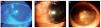

Con respecto a las alteraciones corneales (Figura 3), se encontraron 28 pacientes (50.9%) con queratitis punteada superficial (28 de 28 tenían ≥1+), 11 (20%) tuvieron pannus, nueve (16.4%) presentaron infiltrados corneales, cuatro (7.3%) adelgazamiento corneal, cinco (7.3%) queratitis ulcerativa periférica, tres (5.5%) úlceras corneales y dos (3.6%) vascularización estromal (Tabla 3).

Figura 3. Alteraciones corneales secundarias a rosácea ocular. A) Erosiones epiteliales y queratitis punteada superficial, B) formación de pannus corneal, C) vascularización e infiltración inflamatoria con adelgazamiento estromal.

Analizando por separado las manifestaciones cornéales, las más frecuentes fueron: queratitis punteada superficial en 28 (50.9%) pacientes, similar a lo reportado por Pisella13 de 46% y a la observada por Barankin y Guenther7 de 41%. Seguida por pannus en 11 (20%) e infiltrados cornéales en nueve (16.4%) casos, cifra que se coloca en la mediana reportada por Kheirkhah23 de 5% a 30% de los pacientes, así como queratitis ulcerativa periférica en cinco (9.1%) y adelgazamiento corneal en cuatro (7.3%) individuos (Figura 3).